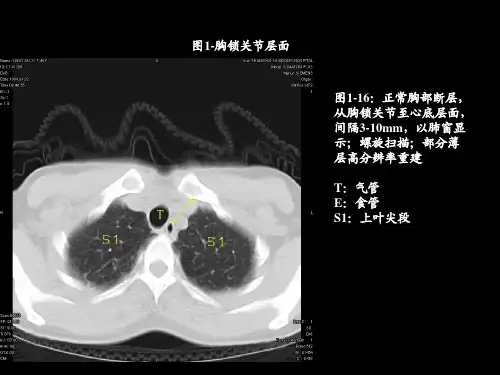

胸部结节病CT影像表现林建煌;于红;李惠民【摘要】Purpose: To analyze the CT findings of thoracic sarcoidosis and find out typical and atypi cal features, in order to improve the recognition and diagnosis. Methods: The CT scans of 38 patients with confirmed thoracic sarcoidosis were retrospectively analyzed. The patients included 12 males and 26 female, and the age range from 17 to 56 years (mean 45.2 years) . The scan thickness was 7mm or 5mm,and the reconstruction thickness was Imm or 1.25mm. Thirty - two of them were undergone enhanced scanning. Results: The enlargement of lymph nodes was seen in all patients. Thirty - three patients (86.8%) had typical pattern of enlargement of lymph nodes in symmetrical, bilateral hilar, right- sided paratracheal and aorta - pulmonary window. The others was atypical. Pulmonary changes were seen in 21 patients(55.3 % ) . Among them, 12 patients (57.1% ) had typical reticulonodular changes. An extraordinary finding including patchy, irregular nodule, and reticulation in bilateral lung base was found in 5 patients. Three of them were also had atypical lymph nodes. Conclusion: The typical pattern of enlargement of lymph nodes in symmetrical, bilateral hilar, right - sided paratracheal and aorta - pulmonary window was seen in most patients with thoracic sarcoidosis, which would be specific. The patchy, irregular, and reticular lesions in bilateral lung base might be an indicative for the diagnosis of thoracic sarcoidosis.%目的:分析胸部结节病cT影像,探讨其典型性及小典型件,以进一步提高认识,帮助诊断.方法:回顾性分析38例确诊的胸部结节病CT图像,男12例,女26例,年龄17-56岁,平均45.2岁CT扫描层厚7mm或5mm,同时均有1mm或1.25ram薄层图像,32例完成增强扫描结果:全部有肺门或纵隔淋巴结肿大,典型)双侧肺门对称件淋巴结肿人及纵隔右气管旁和主肺动脉窗淋巴结肿大33例(86.8%).出现肺部病,变21例(55.3%),典型网织结节改变12例(57.1%),5例出现奇特的双下肺斑片和不规则结节伴有网格线影.不典型淋巴结表现的5例结节病中3例有奇特肺内改变.结论:胸部结节病多数有双侧肺门对称性淋巴结肿大及纵隔右气管旁和主肺动脉窗淋巴结肿大的典型表现,有高特异性.奇特的双下肺斑片和不规则结节伴有网格线影可能有助于不典型胸部结节病的诊断.【期刊名称】《中国医学计算机成像杂志》【年(卷),期】2011(017)002【总页数】4页(P118-121)【关键词】结节病;胸部;X线计算机,体层摄影术【作者】林建煌;于红;李惠民【作者单位】福建省漳州市中医院(福建中医药大学附属漳州中医院)放射科;第二军医大学附属长征医院影像科;上海交通大学医学院附属新华医院放射科【正文语种】中文【中图分类】R445.3结节病是一种病因不明、以非干酪性肉芽肿为特征的系统性、自身免疫性疾病,可累及全身多个系统和脏器,胸部是结节病最好发的部位。